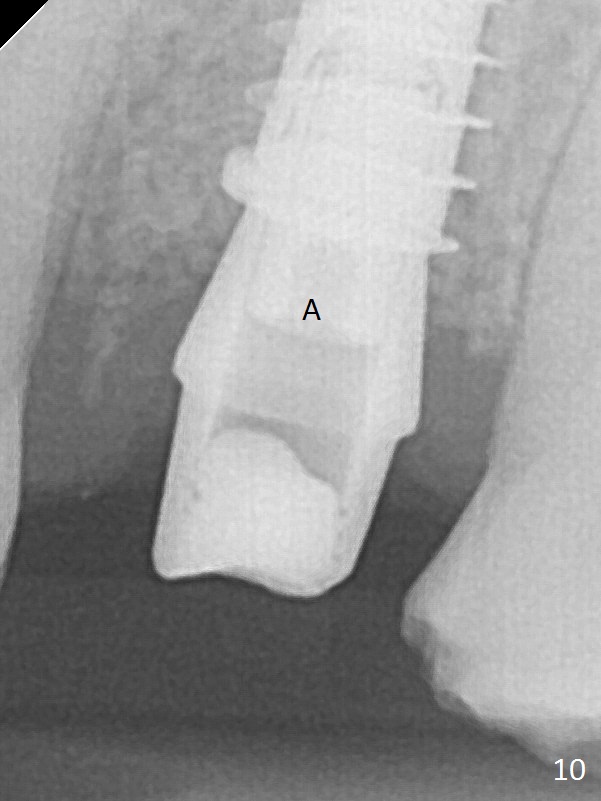

The buccal gingiva over the tooth #13 (Fig.1 white *) with crack (Fig.2 (mesial view of the extracted tooth)) is erythematous with deep buccal (B) pockets, which do not appear to extend the level of exostosis of the neighboring teeth (Fig.1 black *), i.e., coronal to the apical end of the crack with granulation tissue (Fig.2 *). Osteotomy is initiated with a 1.6 mm drill in the palatal aspect of the socket (Fig.3) so that an implant will be placed palatal (Fig.8,11) and there is enough buccal gap for bone graft (Fig.8 *). After withdrawal of 3.3 mm Magic Drill (trephine bur), the osteotomy (Fig.4 O) plug (red outline) is intentionally left in situ. When a 4x11 mm dummy implant is placed (Fig.5 (green outline), 6), the plug is compressed (Fig.5). With placement of a definitive implant (4.5x13 mm, Fig.7 (green), 9), the plug as well as the sinus floor (Fig.4 SF) is lifted (Fig.7 red curved line), 9 (arrowheads)). In brief the autogenous bone is used for sinus lift. There is no intra- or post-op nasal hemorrhage. With a small piece of gauze (Fig.8 G) in the implant well, allograft is placed in the buccal (mainly) and palatal gaps until the level of the implant plateau. Then a 4.5x4(3) mm abutment is placed (Fig.9-10 A). Next another piece of gauze is placed in the space corresponding to the abutment cuff (Fig.11 G) for fabrication of an immediate provisional (Fig.12 P). More bone graft is placed in the soft tissue zone (dual zone technique) after gauze removal and before provisional seating. With dual zone bone graft technique and provisional support, the soft tissue atrophy should be expected to be minimal (Fig.12 *). The zone of exostosis (more coronal) should be much less, since the bone density in the zone is high.

The buccal gingival inflammation subsides 1 week postop (Fig.13,14). There is no bone loss 4 months postop (Fig.15,16). The crown is recemented 6 months post cementation (probably due to short abutment); there is a residual cement (Fig.17 <), which is removed (Fig.18).